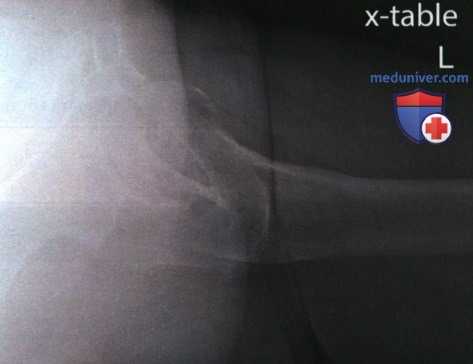

Рекомендации по анализу рентгенограммы тазобедренного сустава в аксиолатеральной проекции (нижневерхней, по методу Данелиуса-Миллера)

Рекомендации по анализу качества изображений (рис. 1):

РИСУНОК 1 Рентгенограмма тазобедренного сустава в аксиолатеральной проекции, правильное расположение.

• Мягкие ткани противоположного бедра не накладываются на головку бедренной кости или ее шейку

• Вертлужная впадина визуализируется в профиль.

• Верхняя ветвь таза видна медиальнее головки бедренной кости (рис. 4)

• Отсутствует проекционное укорочение шейки бедренной кости

• Большой и малый вертелы визуализируются приблизительно на одном уровне (рис. 5)

• Малый вертел виден в профиль сзади.

• Большой вертел накладывается на диафиз бедренной кости (рис. 6)

• Перелом проксимального отдела бедренной кости или ее шейки: рис. 7

• Вывих тазобедренного сустава: рис. 8

• Шейка бедренной кости находится в центре экспозиционного поля

• Вертлужная впадина, большой и малый вертелы, головка и шейка бедренной кости, седалищный бугор входят в экспозиционное поле

РИСУНОК 2 Правильное положение пациента для рентгенографии тазобедренного сустава в аксиолатеральной проекции. РИСУНОК 3 Правильные наклон таза, угол между бедренной костью и ЦП и положение ПИ для рентгенографии правого тазобедренного сустава в аксиолатеральной проекции (угол между ЦЛ и бедренной костью составляет 45°). РИСУНОК 4 Рентгенограмма тазобедренного сустава в аксиолатеральной проекции без наклона таза. Верхняя ветвь таза накладывается на головку бедренной кости и ее шейку. РИСУНОК 5 Рентгенограмма тазобедренного сустава в аксиолатеральной проекции. Угол между бедренной костью и ЦП был избыточным. РИСУНОК 6 Рентгенограмма тазобедренного сустава в аксиолатеральной проекции. Нижняя конечность была повернута наружу.